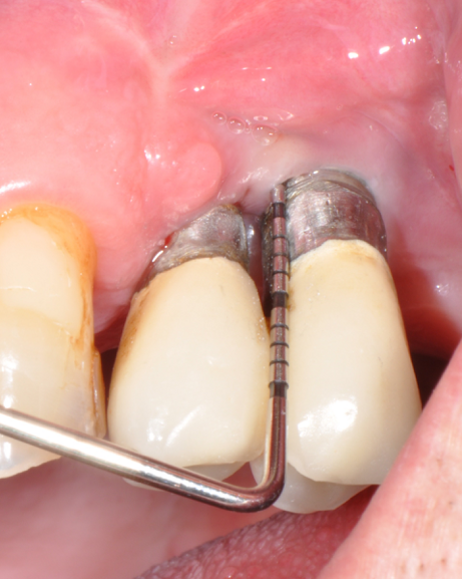

The parameters used to define peri-implant disease usually are: Probing Depth (PD), Crestal Bone Loss (CBL), Bleeding on Probing (BOP) and presence of suppuration and/or fistula.9 Peri-implant mucositis is characterised by soft tissues inflammation witnessed by BOP with or without PD deepening but no effects on the crestal bone while peri-implantitis is characterised by CBL, BOP alone or in conjunction with pus, with or without PD deepening. (Figs. 1, 2 and 3) display the diagnostic steps of a case of peri-implantitis. While mucositis allows a complete healing, peri-implantitis is not reversible.12

Fig.1: Case 1. Peri-implant probing reveals a PPD of 9mm and pus.

Fig.2: Case 1. BOP starts immediately after probing.